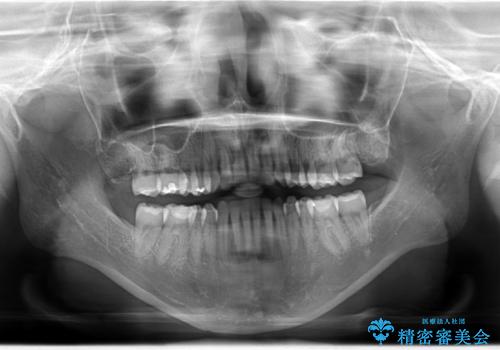

Invisalign インビザライン によるガタつき、受け口傾向の改善

奥歯の位置関係の修正は難儀することが多いマウスピース矯正ですが、割とスムーズに奥歯の位置関係の修正をすることができました。

クロスバイトもきれいになり、きれいな歯並びとなりました。